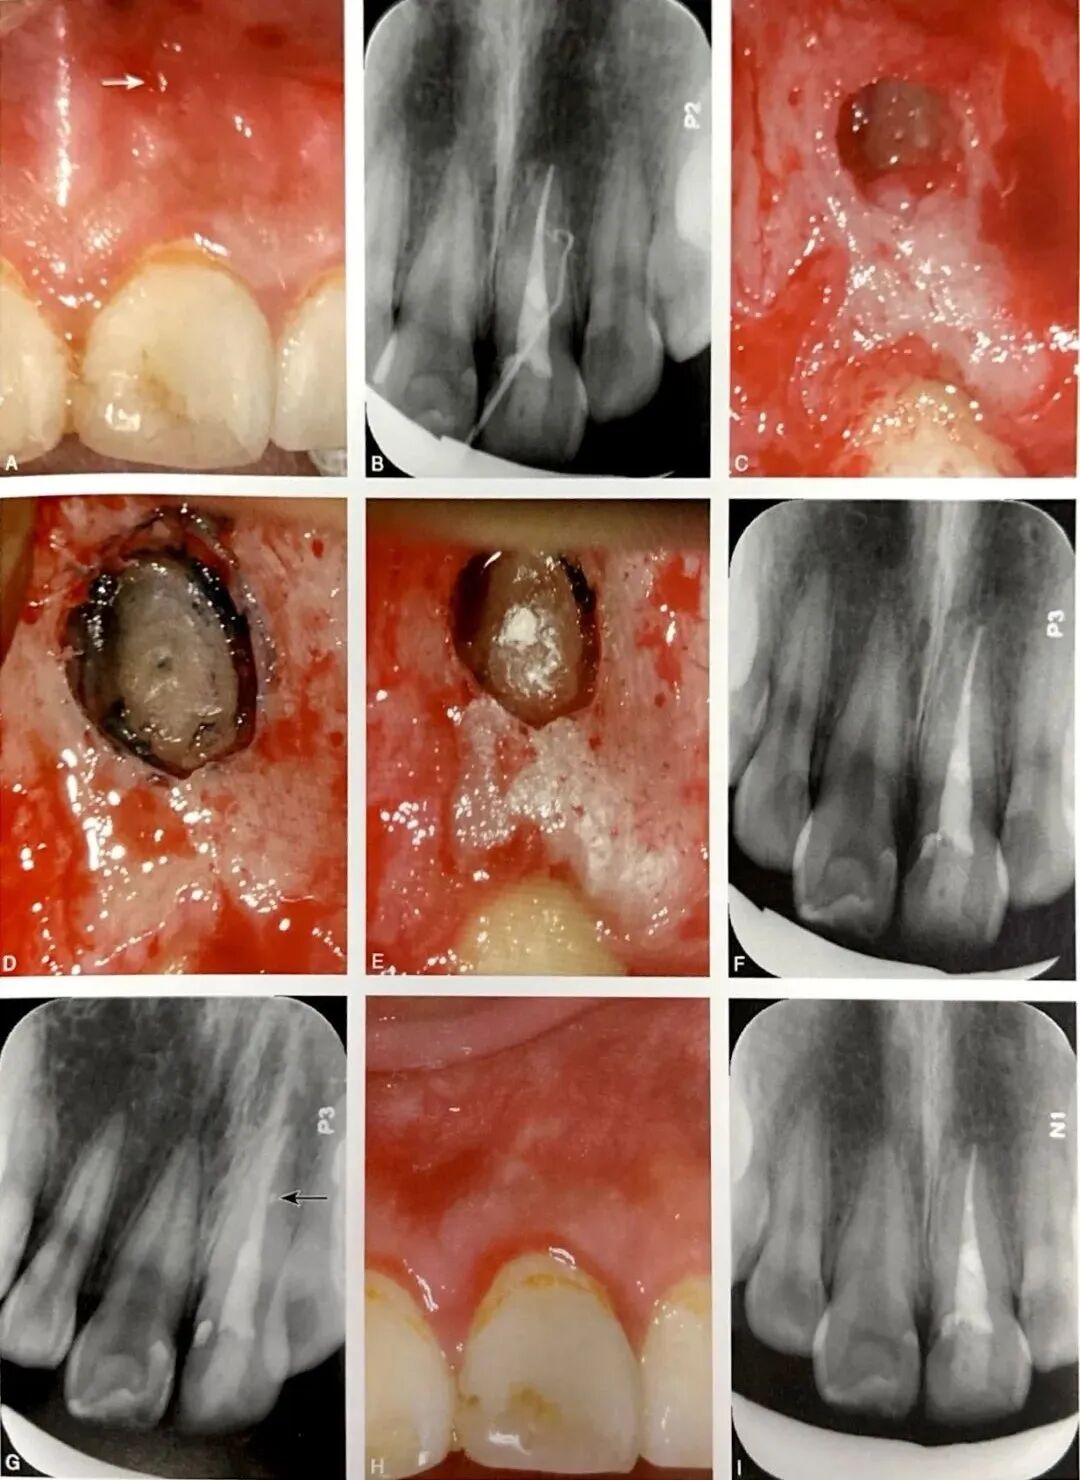

根管侧支通常位于根尖区,少数位于根中段。根尖区以及根中段唇颊侧的根管侧支易诊断,如图5所示,A为口内像颊侧面观示左上中切牙根中段窦道(箭头);B为牙胶示踪根尖片,示窦道来源于牙根中段远中;C为左上颌中切牙行显微根尖外科手术,切开翻瓣牵拉见颊侧根中段骨质缺损;D为刮治后染色见根管侧支;E为根管侧支逆行预备和充填;F为术后根尖片;G为偏角投照根尖片示充填后侧支(箭头);H为术后4个月随访口内像示牙龈和牙槽黏膜正常根尖片,可见根尖周和根周正常;根中段近远中侧或者舌腭侧的根管侧支易漏诊,应使用显微口镜反射观察,必要时行意向再植术,患牙微创完整拔出后在体外全面探查。探查时,根管侧支可有不同着色,蓝黑色(未充填)最为常见,其他有白色(糊剂充填)和黄色、红色、蓝色等(牙胶充填)。